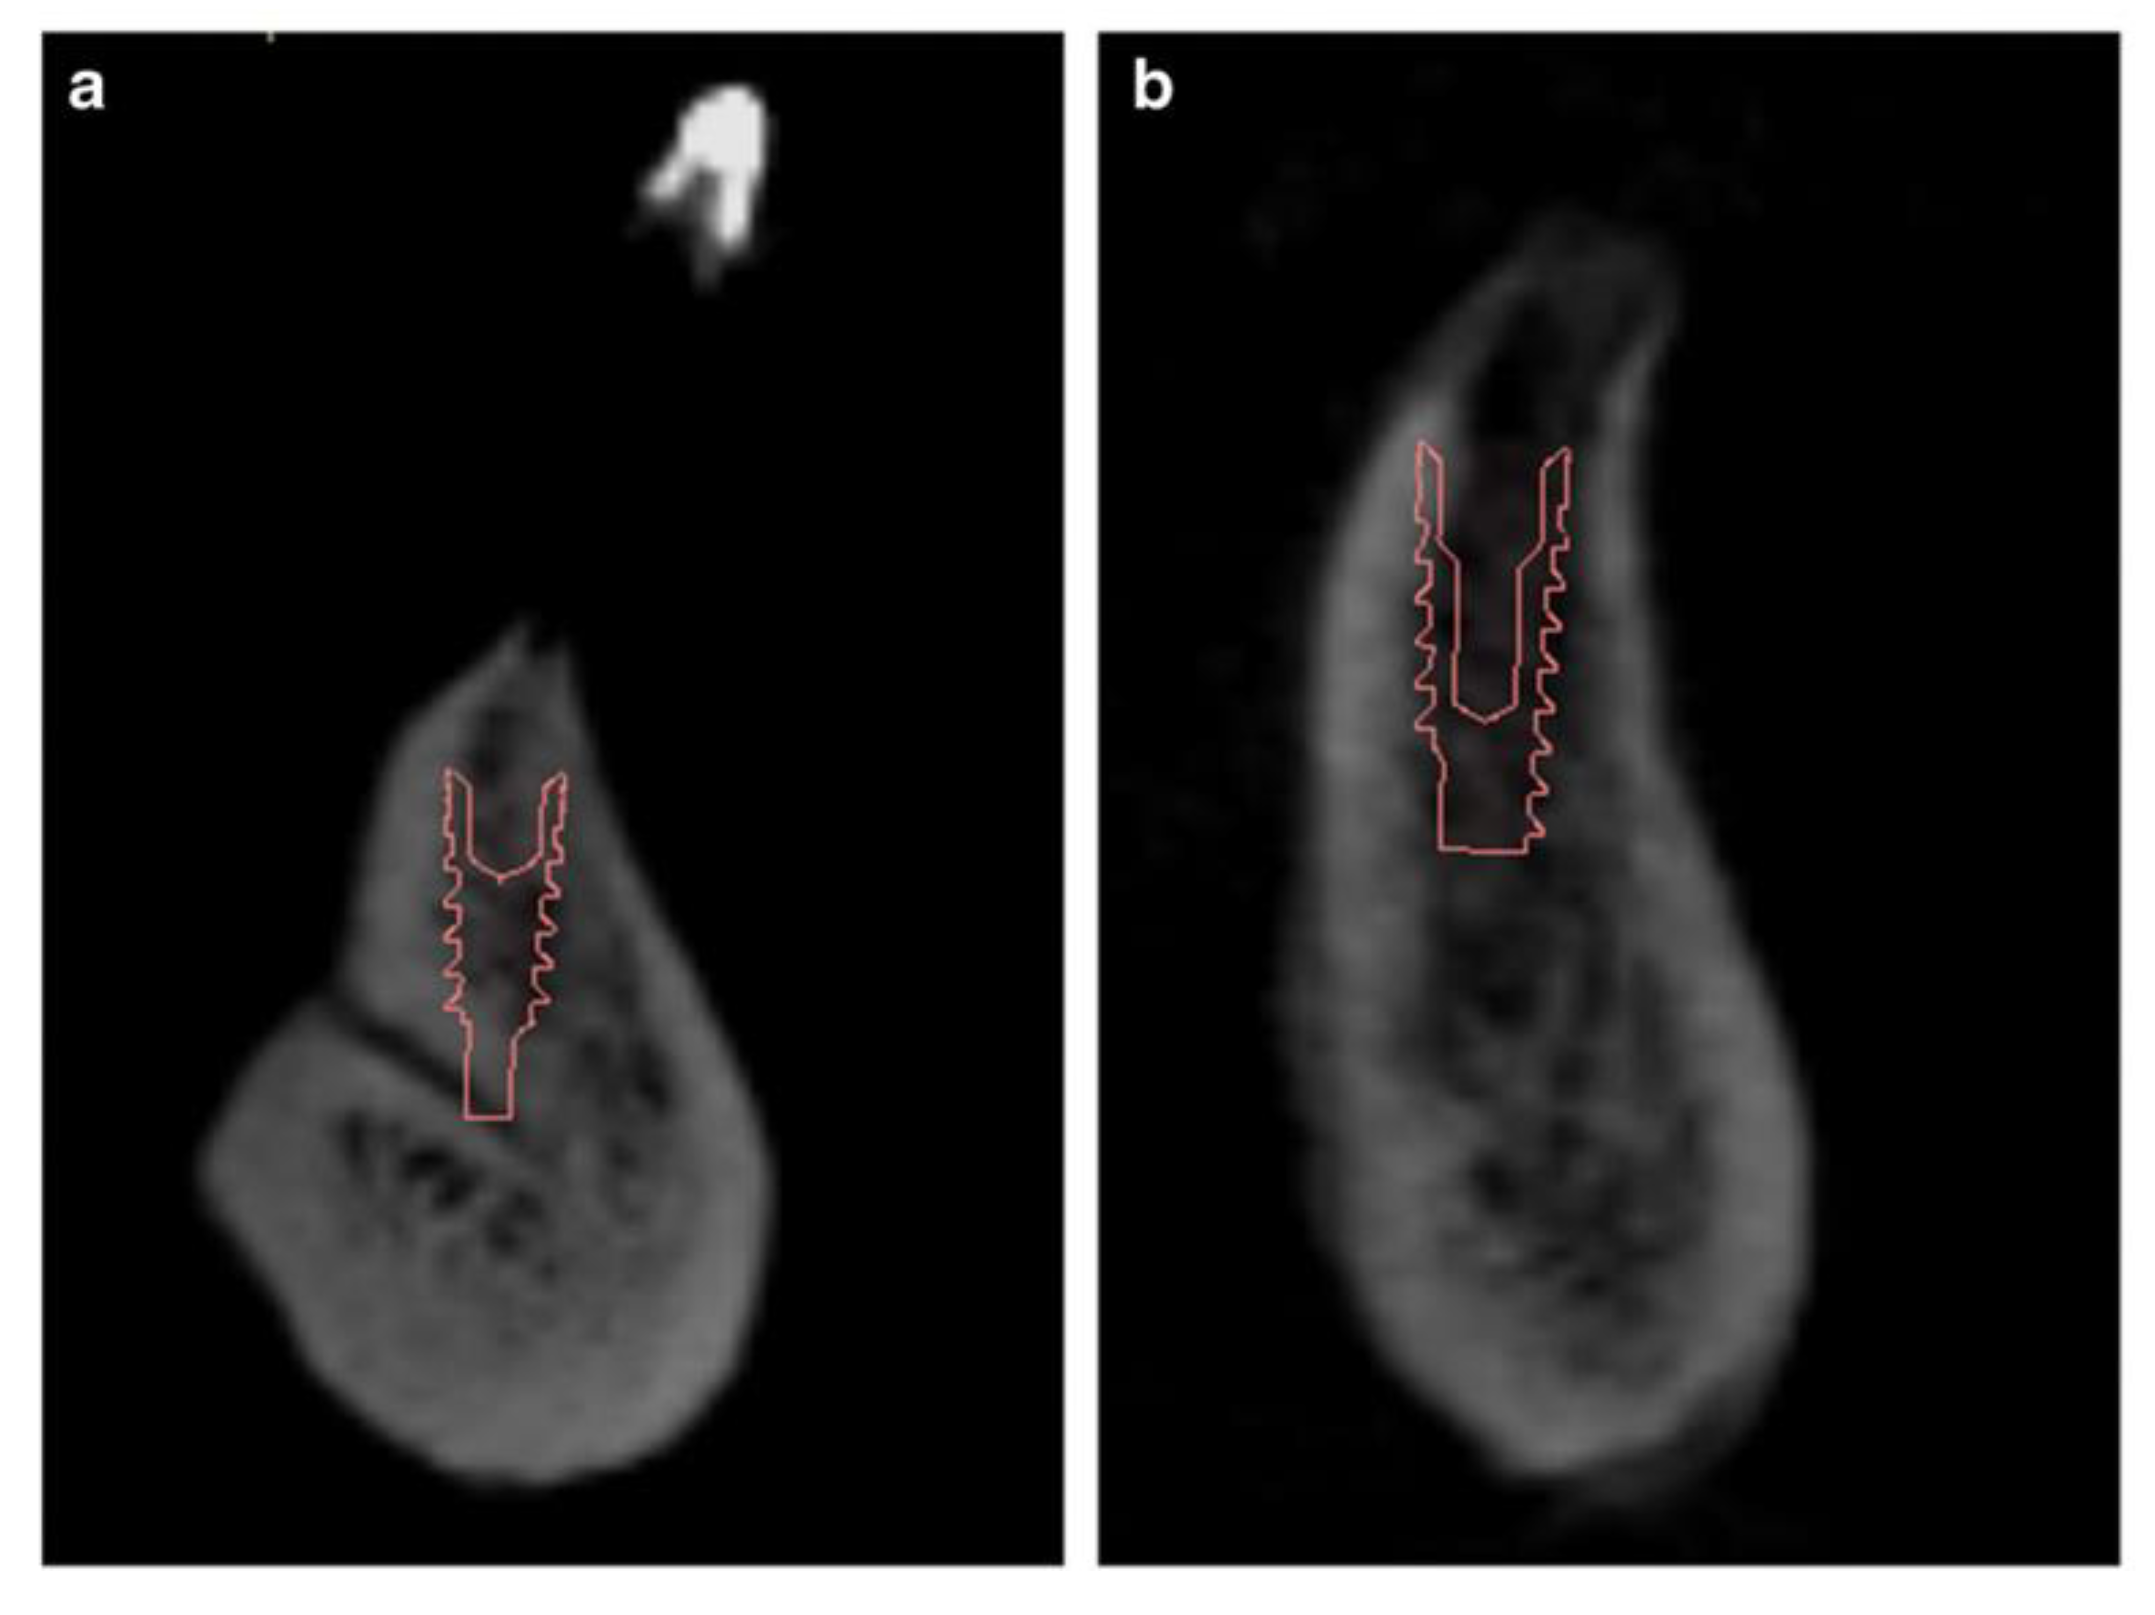

CBCT in the Post-Surgical Phase: Assessment of Bone Loss and Post-Operative Surgical Complications